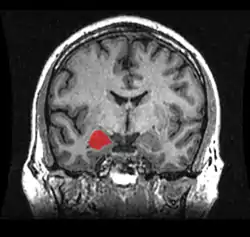

El cuerpo amigdalino, complejo amigdalino o amígdala cerebral es un conjunto de núcleos de neuronas localizadas en la profundidad de los lóbulos temporales de los vertebrados complejos, incluidos los humanos.[1] La amígdala forma parte del sistema límbico, y su papel principal es el procesamiento y almacenamiento de reacciones emocionales.[2][3]

Las regiones descritas como «amígdala» en realidad abarcan una serie de núcleos con distintos atributos funcionales llamada complejo amigdalino. Entre esos núcleos se encuentra el grupo basolateral, el núcleo centromedial y el núcleo cortical. El grupo basolateral se puede dividir a su vez en el núcleo lateral, el basal y los núcleos basales accesorios.[2][4]